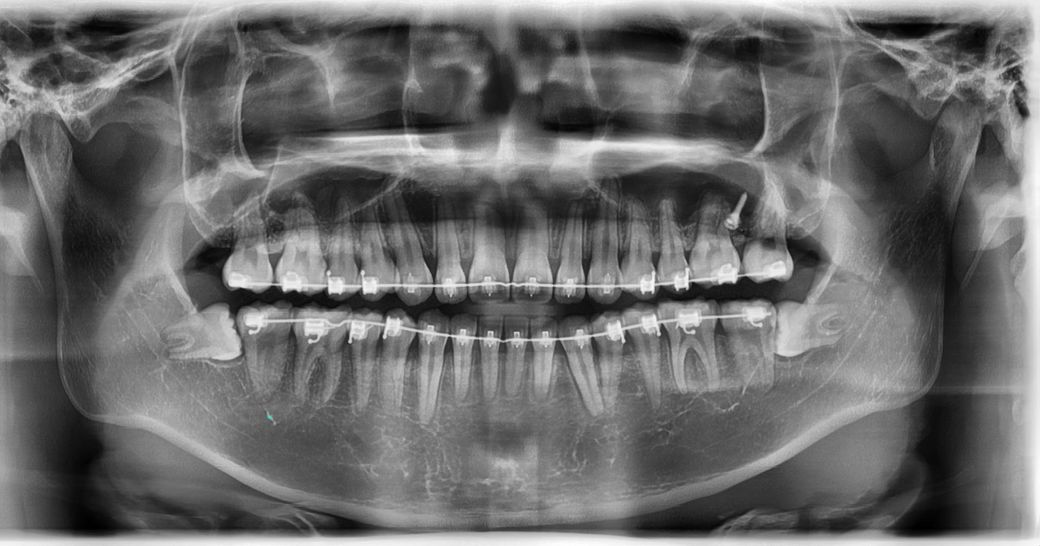

아이 치아 사진입니다.

하악 왼쪽 송곳니와 상악 송곳니 뿌리가 소구치쪽으로 쓰러져 있어요.

상악 송곳니는 교정전보다 조금 더 쓰러진 느낌이고 하악 송곳니는 교정전보다 많이 쓰러진 느낌입니다

• 1번 째 사진

사진으로 봤을 때 송곤이 치아 뿌리에 각도는 이상이 없는 것으로 보입니다. 또한 파노라마 사진은 이 차적으로 보는 사진이기 때문에 정확한 뿌리의 각도를 보인다기보다 경우에 따라서는 겹쳐 보이는 것처럼 느껴질 수 있습니다.

1. 교정 시 치아 머리 부분만 움직여 치축이 틀어진 것 같습니다 이미 배열이 완료되어 공간이 닫힌 경우 치근 이동 개선이 쉽지는 않습니다

2. 엑스레이상 거의 붙어있을정도로 근접해보여도 왜곡이 있어서 그럴 수 있습니다

3. 실제로 두 치근이 너무 근접하면 치근흡수의 가능성이 있고, 치아가 힘을 받는 장축방향이 수직이 아니면서 힘을 과도하게 받을 수도 있습니다